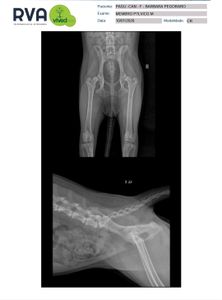

Ela ficou e é parte da família. Mas há pouco tempo descobrimos algo que tirou nossa paz: Pagu foi diagnosticada com Displasia Coxofemural Severa.

Ela mal consegue dormir de dor e está com muita dificuldade pra andar, começando a arrastar as patinhas de trás.

Cada dia ela piora e pode deixar de andar completamente, e a dor está cada vez mais intensa (ela grita de dor mesmo analgeseada).

A Pagu precisa passar urgentemente por uma cirurgia que vai aliviar a dor, trazer a mobilidade de volta e permitir que ela continue vivendo com dignidade. Estamos contra o tempo agora.

O valor total do procedimento + exames é de aprox. R$4200 (para cada lado), um custo que, neste momento, não conseguimos arcar sozinhas. A cirurgia não é estética nem opcional: ela é necessária para que ela não continue sofrendo e para evitar o agravamento do quadro. Com essa cirurgia ela tem chance de ter uma vida próxima do normal em pouco tempo, pois ela é jovem (uma filhotona de cerca de 8 meses).

Essa campanha tem como objetivo arrecadar o dinheiro para a cirurgia do lado direito, que é o mais comprometido, e precisa ser realizada primeiro.